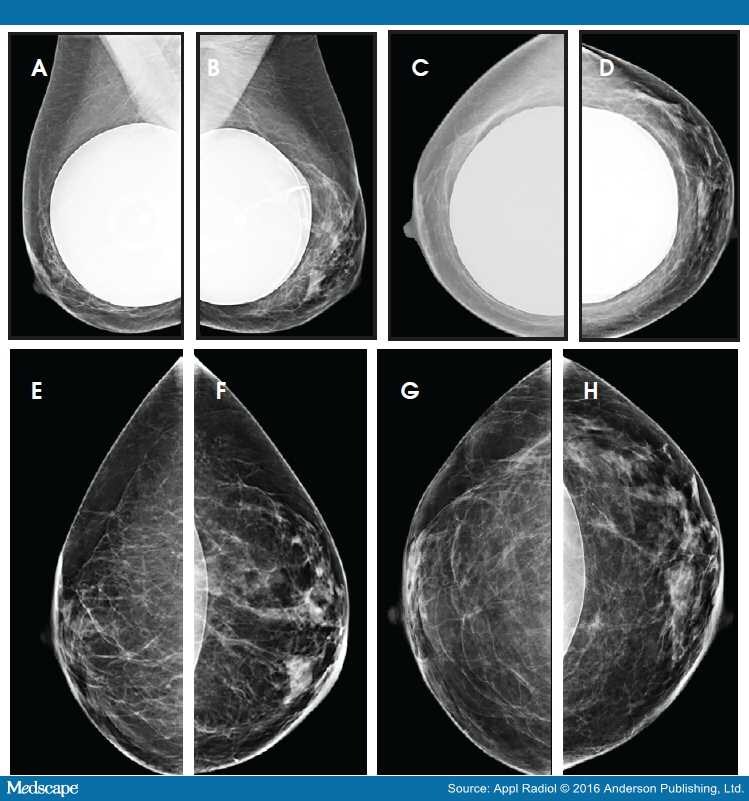

From www.medscape.com

Cosmetic Breast Augmentation Mammographic Findings Manually Flip Breast Implant  Breast implant flipping is really just what it sounds like: The implant flips over in the breast pocket. What is breast implant flipping? When implant flipping does occur, it can usually be fairly easily flipped back by women themselves, typically by leaning forward and making space for the implant in the pocket to allow for manual flipping back into place.. Manually Flip Breast Implant.